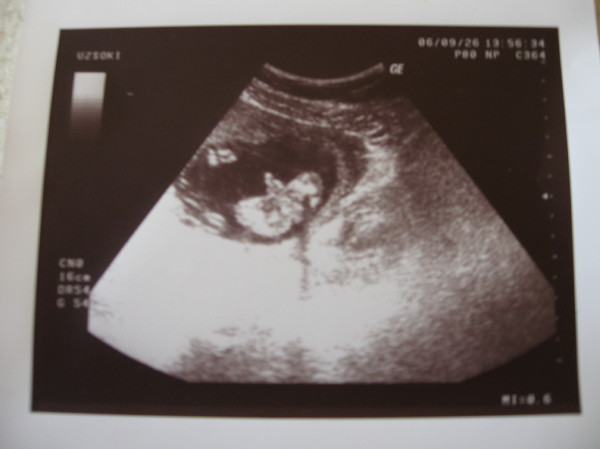

Ha ez igy lenne, ahogy mondjak: lanyok aktivak, fiuk lustak, akkor nagy bajban lennek, mert Zsebibaba NAGYON aktiv - marpedig o hatarozottan fiu! Itt egy kep, nezd meg!

Zsebibaba 130 napos es kisfiu :)

Kép

Az ott kozepen nem a keze, hanem a kukija! A hatan fekszik, alul latszik a ket felgomb-popsija, es a kukija az egnek mered - hatulrol van a kep, semmi mas nem is latszik, csak a ket felhuzott laba meg a kukija hatulrol. Eleg egyertelmuen krapek. EEEEES megis orokke mozog, meg iccaka is! Szoval ezeknek a nepi okossagkonak nem kell beodlni - addig amig kukit nem latsz Kiran, addig o kislany :D